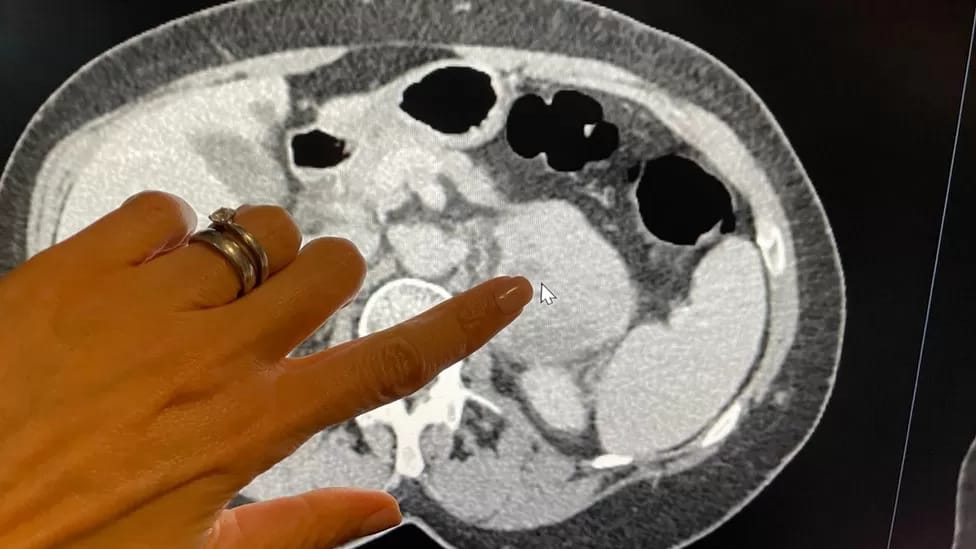

CIENTÍFICOS CON NUEVA IA QUE

DIAGNOSTICA CÁNCER RAROS

Científicos han descubierto una nueva herramienta de IA que es casi el doble de efectiva que los métodos actuales para evaluar un cáncer raro. ¡Puede detectar detalles invisibles para el ojo humano con un asombroso 82% de precisión!

La IA ya está mostrando su valía en el diagnóstico de los cáncer. Los científicos están entusiasmados con su capacidad para mejorar los resultados de los pacientes a través de diagnósticos más rápidos y tratamientos más personalizados y efectivos.

¡Se espera que esta tecnología revolucionaria se utilice en todo el mundo, permitiendo tratamientos específicos para pacientes de alto riesgo y evitando tratamientos innecesarios para aquellos de bajo riesgo!